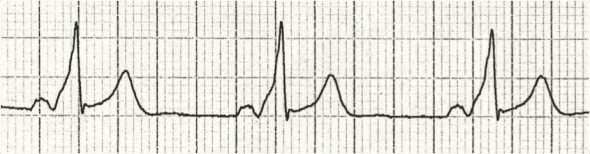

ECG Example – J Wave (Osborne Wave)

A narrow notch can be seen at the J point (junction between the end of QRS and ST segment), that is the J wave. This ECG is secondary to hypothermia.

https://litfl.com/osborn-wave-j-wave-ecg-library/

© Life in the Fast Lane. Licensed under CC BY-NC 4.0